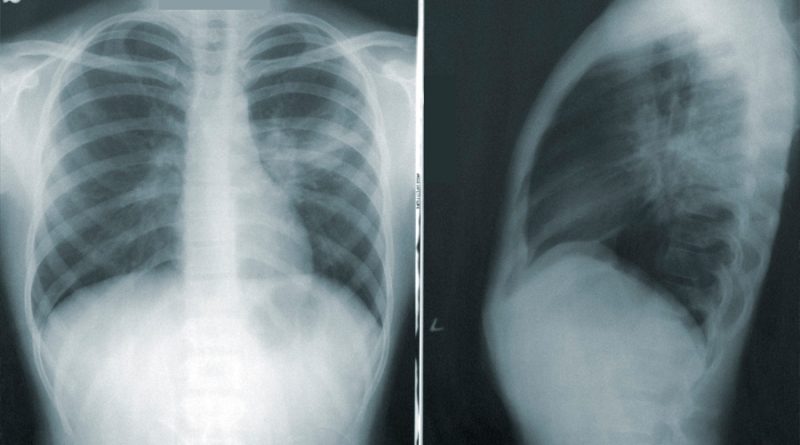

“Me parece el colmo esta respuesta, mi padre tiene tos porque tiene problemas respiratorios que le causó el cigarrillo. Sin la placa del tórax no lo puede atender el neumólogo y menos tratarlo”, sostuvo el denunciante.

Por lo anterior, la fuente pidió que los centros de imágenes diagnósticas sean más flexibles con estas medidas, pues es “ilógico que una persona con este cuadro clínico producido por la nicotina sea enviada a un centro asistencial y se nieguen a realizarle la placa”.